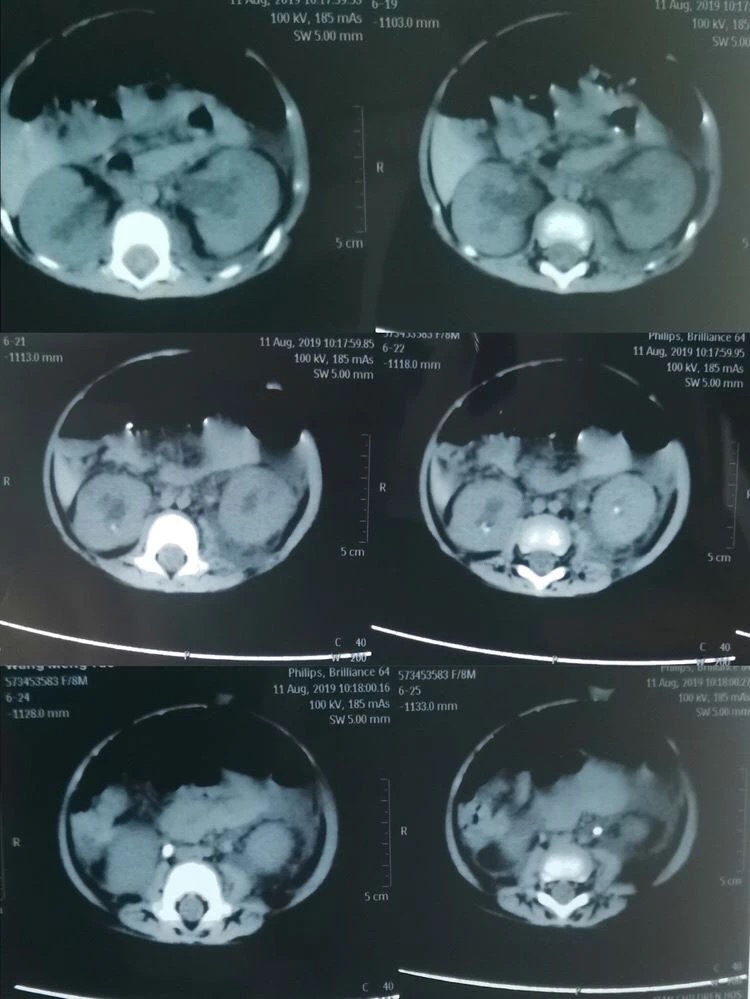

可谁知经过数天的治疗孩子的病情却丝毫未见好转,反而出现了无尿的症状。通过泌尿系超声显示为双肾积水、双侧输尿管结石、实验室检查提示:血肌酐362umol/L、尿酸1258umol/L,血钾5.58mmol/L(正常值为3.5-5.3mmol/L),诊断急性肾功能衰竭。由于当地医疗条件有限,无法完成婴儿碎石手术,一家三口不远千里来到了西安市儿童医院。西安市儿童医院根据孩子的病情,急诊血液透析治疗。由于多日的病痛折磨及血液透析带来极大不适,小瑶瑶精神状态极差,几乎哭不出声音来。可怜天下父母心,看着孩子被病痛折磨,父母的心里真是又急又痛。儿童医院的医生建议小瑶瑶的父母带孩子到男同视频 泌尿外科,向有多年处理婴幼儿结石经验的何士军主任求治。

自2008年三聚氰胺事件后,男同视频 泌尿外科何士军主任带领的团队已累计为超过约400名儿童患者治愈了泌尿系统结石疾病,有着丰富的治疗经验和完备的碎石取石设备。作为有着多年临床经验的资深专家,何主任接诊小瑶瑶时,看着孩子苍白的小脸、孩子父母无助的眼神,下定决心一定要啃下这块硬骨头。在何主任组织下,科室副主任马龙、主治医师李涛、张倩护士首当其冲,迅速完善各项术前准备工作。同时积极与儿科、麻醉科等相关科室组织讨论。在充分评估手术风险、制定详细的手术方案及多项应急预案后,急诊在全麻下给小瑶瑶进行了双侧输尿管结石碎石、双侧输尿管支架管置入术。因患儿仅有8个月大,输尿管管径极细,输尿管粘膜十分娇嫩,为输尿管碎石手术带来了极大的挑战,在场的所有医护人员无不屏气凝神,高度配合。再看何主任沉着泠静、手下娴熟的进行着碎石取石操作。当双侧输尿管支架管顺利放置于正常位置后,两颗幼小的肾脏再次排出久违的尿液时,在场所有人这才松了一口气。没有雷鸣般的掌声,也没有相互兴奋的击掌庆贺。有的只是每个人内心深处那份遵循患者利益至上的职业荣誉感。